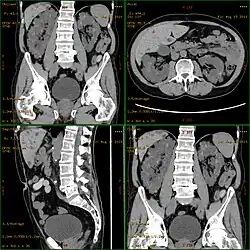

| Diagnostic method | MRI, CT scan, Ultrasound[1] |

Diagnosis may be suspected from one, some, or all of the following: new onset flank pain or red urine; a positive family history; palpation of enlarged kidneys on physical exam; an incidental finding on abdominal sonogram; or an incidental finding of abnormal kidney function on routine lab work (BUN, serum creatinine, or eGFR). Definitive diagnosis is made by abdominal CT exam.

Polycystic kidney disease can be ascertained via a CT scan of abdomen, as well as an MRI and ultrasound of the same area.[23] A physical exam/test can reveal enlarged liver, heart murmurs and elevated blood pressure.[1]